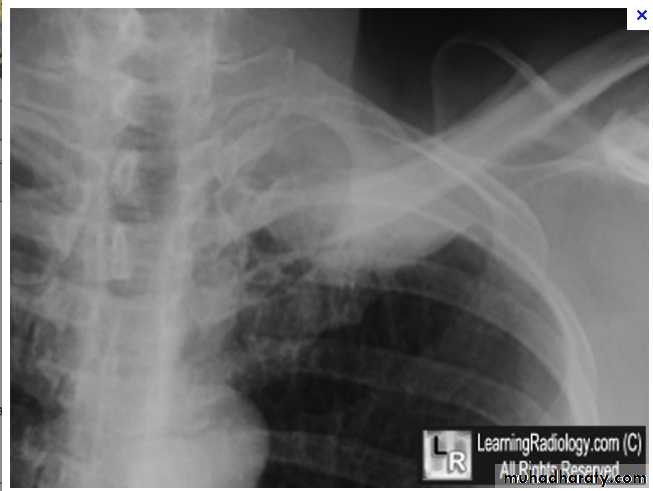

Nodular (coin) lesion in the left upper lung with irregular edge (most probably cancinoma